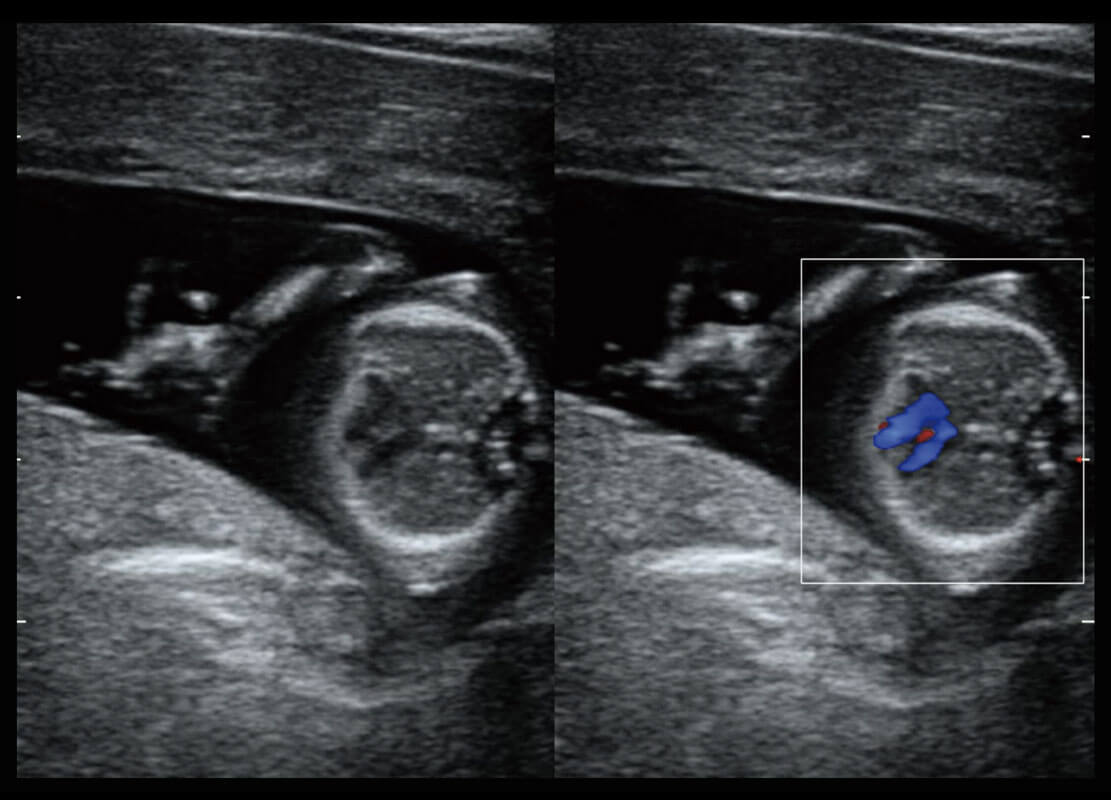

P60搭載一系列胎兒心臟成像技術(shù),實現(xiàn)精細的胎兒心臟評估。

四腔切面

四腔心血流